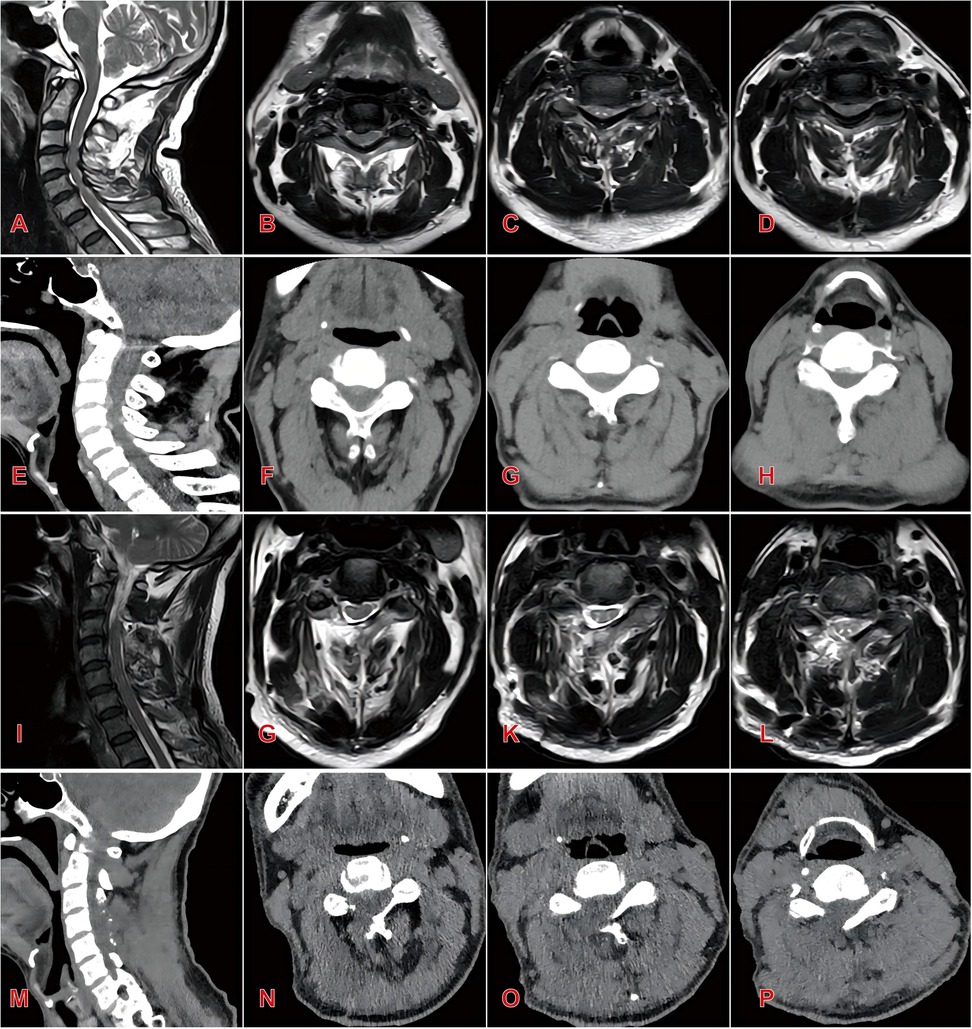

Objective: This study investigates the clinical efficacy and safety of large-channel endoscopic unilateral laminotomy decompression for the treatment of multilevel cervical spinal canal stenosis. Methods: A retrospective study was conducted on 36 Cervical spinal canal stenosis patients with radiologically confirmed who underwent surgical treatment between January 2020–December 2023.Patients were divided into two groups according to the surgical method: endoscopic group(n=16) and open group(n=20).Perioperative Parameters(operative duration, incision length, intraoperative blood loss, hospitalization period were record and Clinical efficacy were systematically assessed using validated metrics: Visual Analog Scale, Japanese Orthopaedic Association score, Neck Disability Index. Radiographical parameters (C2–C7 Cobb angle, T1 slope, pavlov ratio (canal/vertebral body diameter)) are used to assess the decompression effect and stability of cervical spine. Results The endoscopic group demonstrated significant advantages over the open group in operative time (1.6 ± 0.6 vs. 2.1 ± 0.2 h, P<0.05), incision length (1.3 ± 0.1 vs. 9.5 ± 0.7cm, P<0.05), blood loss (12.4 ± 7.4 vs. 64.3 ± 19.5 mL, P<0.05), and hospitalization duration (6.6 ± 1.1 vs. 8.6 ± 1.4 days, P<0.05). Both groups showed significant postoperative improvements in VAS, JOA, and NDI scores compared to preoperative baselines (P<0.05). At 1 month postoperatively, the endoscopic group exhibited superior VAS scores to the open group (2.69 ± 0.79 vs. 4.4 ± 0.88, P<0.05), though no significant differences were observed at other time points. Radiographic outcomes at final follow-up revealed significantly better cervical Cobb angle (13.57 ± 2.29° vs. 16.34 ± 2.95°, P<0.05) and T1 slope (22.62 ± 1.51° vs. 25.24 ± 2.41°, P<0.05) in the endoscopic group. Conversely, the open group demonstrated greater postoperative spinal canal area and Pavlov ratio (P<0.05). Complications included 2 cases of C5 nerve root palsy and 1 case of axial pain in the open group, while the endoscopic group had 1 case of transient muscle weakness. No reoperations were required. Conclusion The large-channel endoscopic unilateral laminotomy decompression demonstrates satisfactory short-term efficacy in treating multilevel Cervical Spinal Stenosis with ligamentum flavum hypertrophy. This minimally invasive technique offers significant advantages including reduced surgical trauma, accelerated recovery, enhanced postoperative cervical stability and relatively higher patient satisfaction.